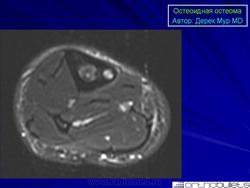

МРТ. Внутрисуставная остеоид остеома

МРТ позволяет изучить не только сам очаг остеоид остеомы, но и окружающий склероз костной ткани, а также смежные с опухолью участки костного мозга и мягкие ткани.

Внутрисуставная остеоид остеома, которая локализуется в пределах сустава, или вблизи от него, считается отдельной клинической единицей. Наиболее часто поражается тазобедренный сустав.

Результаты визуализации внутрисуставной остеоидной остеомы резко отличаются от таковой при интракортикальной остеоидной остеомы.

При внутрисуставных остеоид остеомах реактивная кортикальная реакция минимальна, или отсутствует.